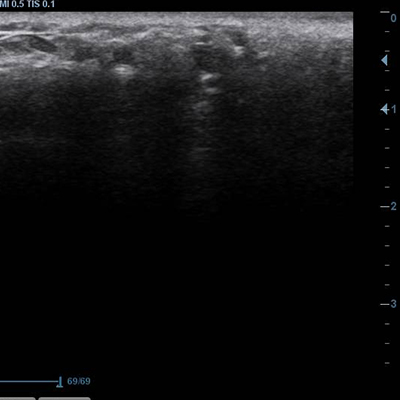

[얼굴이물질제거] 17.01.6 - 이물질제거 - 전후사진

17.01.10 - 이물질제거 - 전후사진